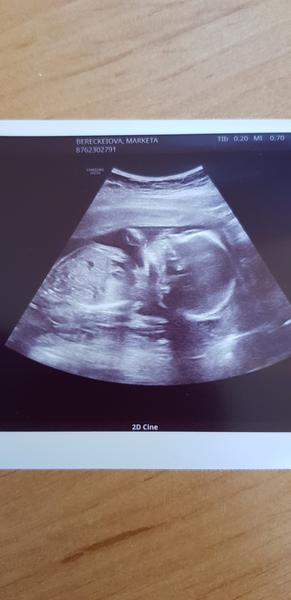

@ja_osobne podle hlavičky vypadá na holčičku,ptala ses na pohlaví? 😀

@juliemichal 😍😍😍 nevydržela jsem, holčička to je, zatím 🤷♀️😂😂😂😍😍😍😍😍

@juliemichal Emily 🥰🥰

Vše v naprostém pořádku 🥰🥰🥰🥰🥰🥰